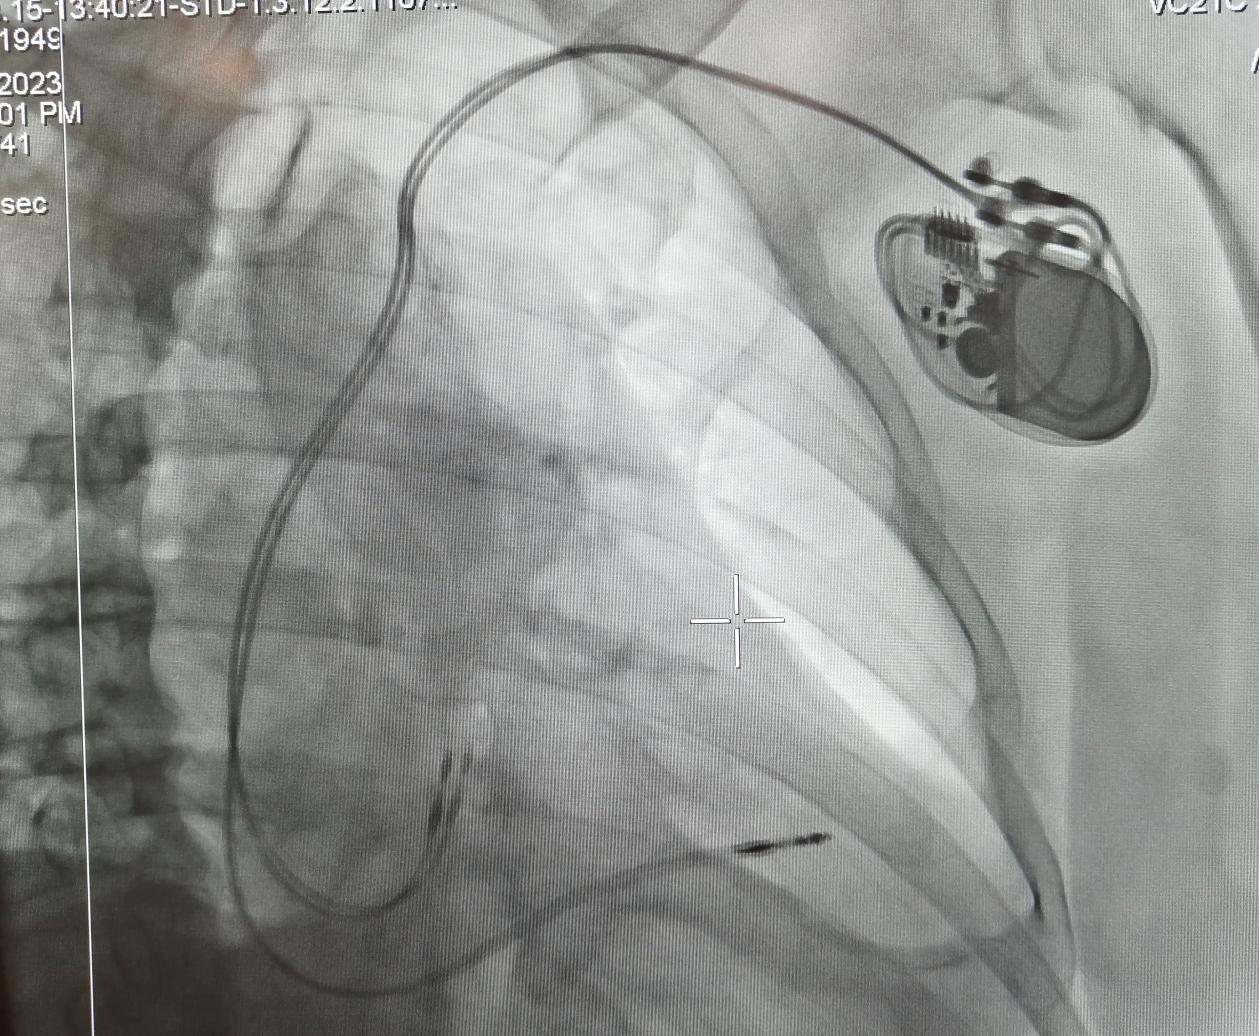

起搏器植入后影像圖